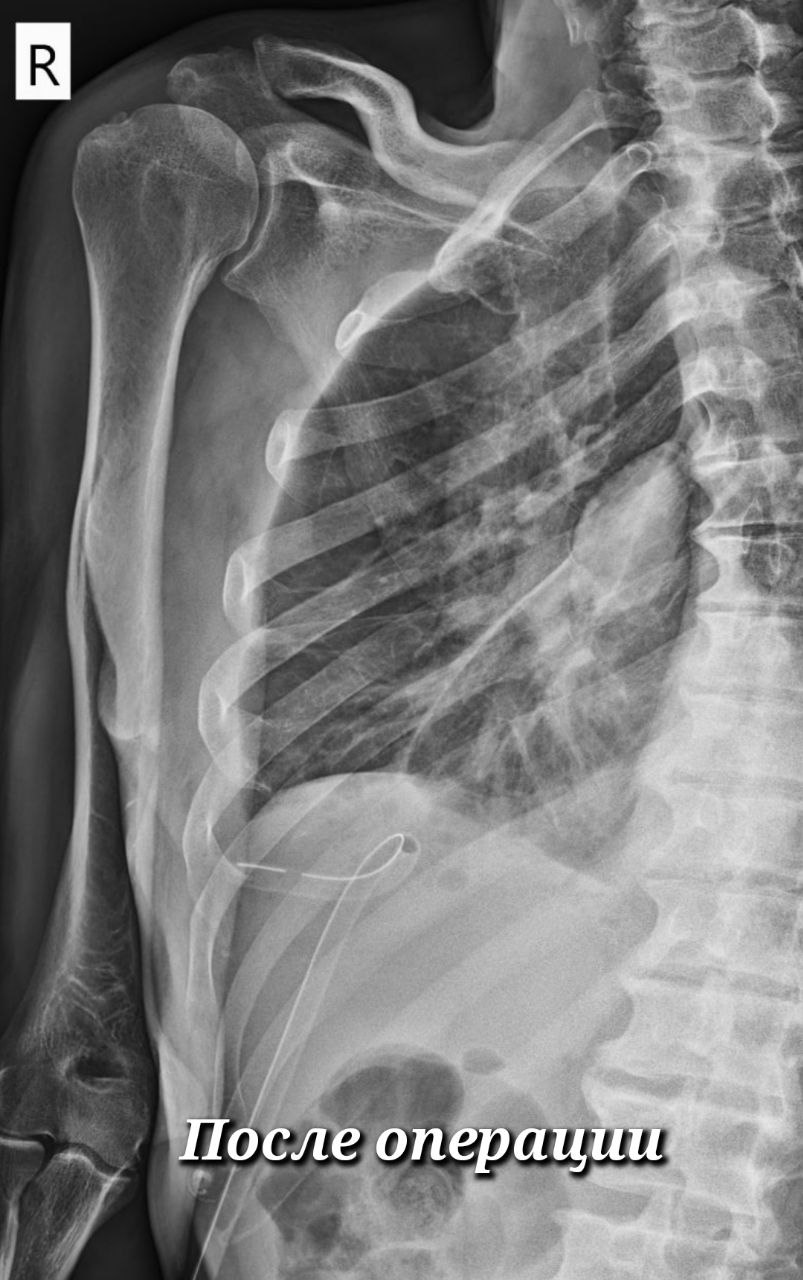

Торакоскопическая методика кропотливая и технически непростая. Через три разреза от 0,5 до 1 сантиметра хирурги специальным инструментом разрушают и удаляют всю патологическую ткань – гнойные полости, спайки, шварты, фибринозные наложения. Двигаться необходимо очень осторожно, чтобы не повредить лёгкое. Работа проводится при повышенной из-за воспаления кровоточивости, а на отдельных участках кратно усложняется множеством тонких и уязвимых сосудов.

-Во время операции наша задача избавиться от очага инфекции и затем проконтролировать, чтобы лёгкое расправилось и приняло своё анатомическое положение. Оно сразу включается в работу и начинает выполнять свою функцию. Послеоперационный период предполагает активное дренирование плевральной полости с периодическими санациями. В среднем лечение такого больного в стационаре сегодня занимает две недели. После открытых операций больные находились у нас по 2-3 месяца и даже после выписки до полугода оставались с множественными дренажами, - объясняет Ринат Рахметов, хирург окружного Центра торакальной хирургии на базе Сургутской травмбольницы.